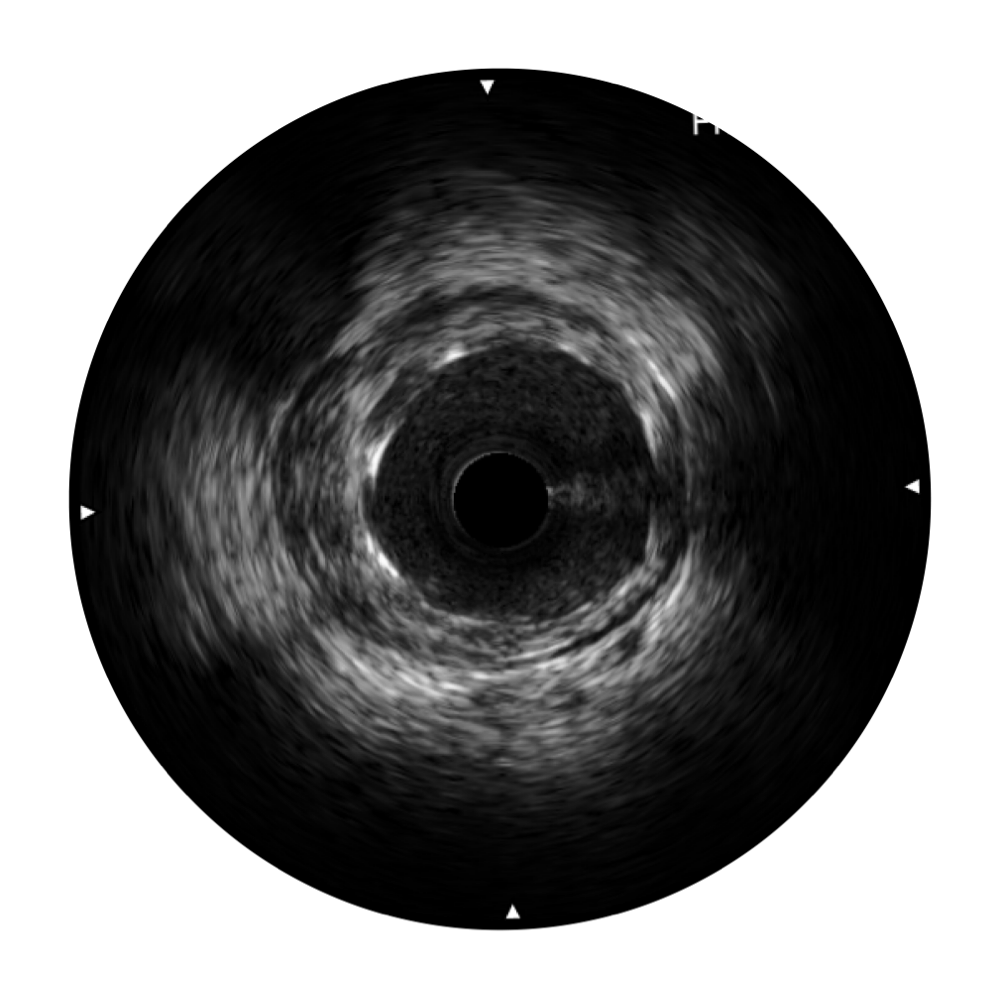

DB中国旗舰官方网站宽频IVUS图像

对比传统IVUS导管成像,DB中国旗舰官方网站宽频IVUS图像的近场支架梁显影更细腻,远场中膜外血管仍清晰可辨,兼顾远中近,兼顾分辨力与穿透深度